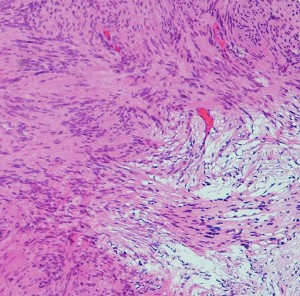

Antoni type A(密な部分)とAntoni type B(そな部分)の混在

紡錐型の核を有する腫瘍細胞で構成されます。左側の写真のように,古典的病理所見として,束状 fascicular に配列する密な組織である Antoni A Typeと網状 reticular で疎な組織である Antoni B Typeが混在するパターンを示します。神経鞘腫では多少の核の異型性がみられても悪性像とはいえません。嚢胞を形成したり,時には毛細血管拡張 simple hemangioma を思わせるような著明な血管の増生があり腫瘍内出血をきたすことがあります。

30代男性の迷走神経鞘腫です。右のように活発に増殖してstreaming patternをとる部分と,左のようにのう胞形成しながら退縮変性 degenerative change している部分が混在しています。若年者の神経鞘腫でも退縮変性はみられます。